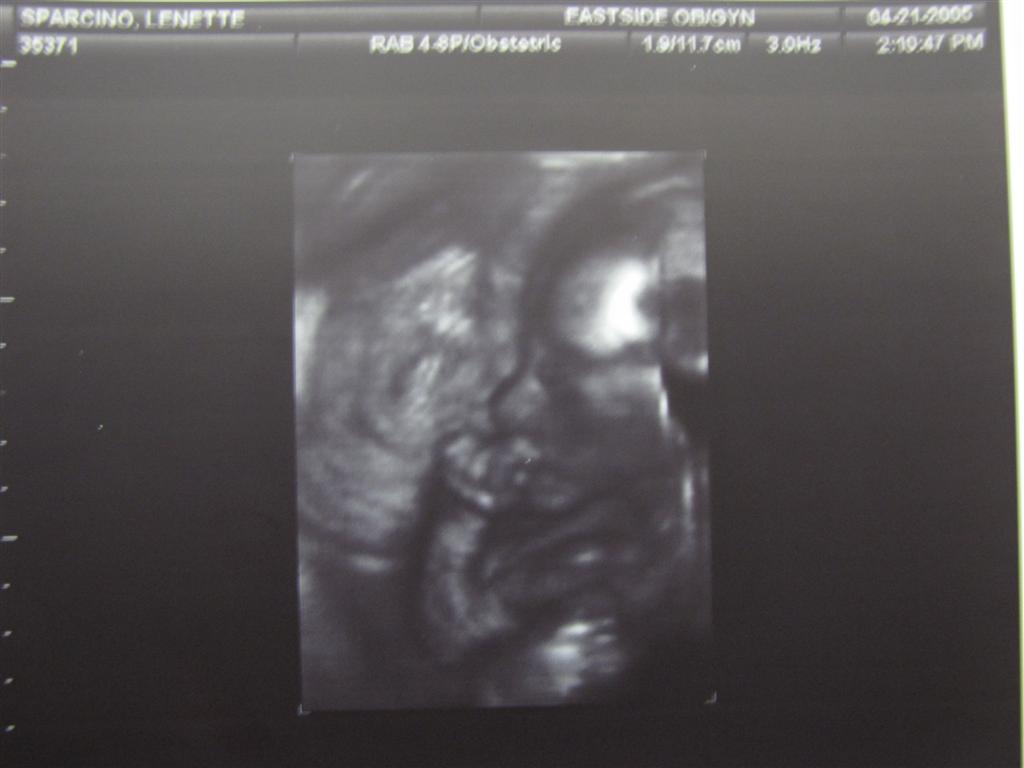

On May 24th, I had busy doctor visit. I was tested for gestational diabetes, the doctor decided that the pregnancy had given me back spasms, I got the last of my steroid shots to help promote lung growth, the ultrasound determined that my cervix had thickened slightly and confirmed that we were still having a girl!

On June 6th, I had an ultrasound and my cervix had once again shortened. My doctor decided that I needed to be in the hospital for observation. I was there from that Monday until Thursday. I wrote in my journal that I was SO glad to get home and back on my couch!